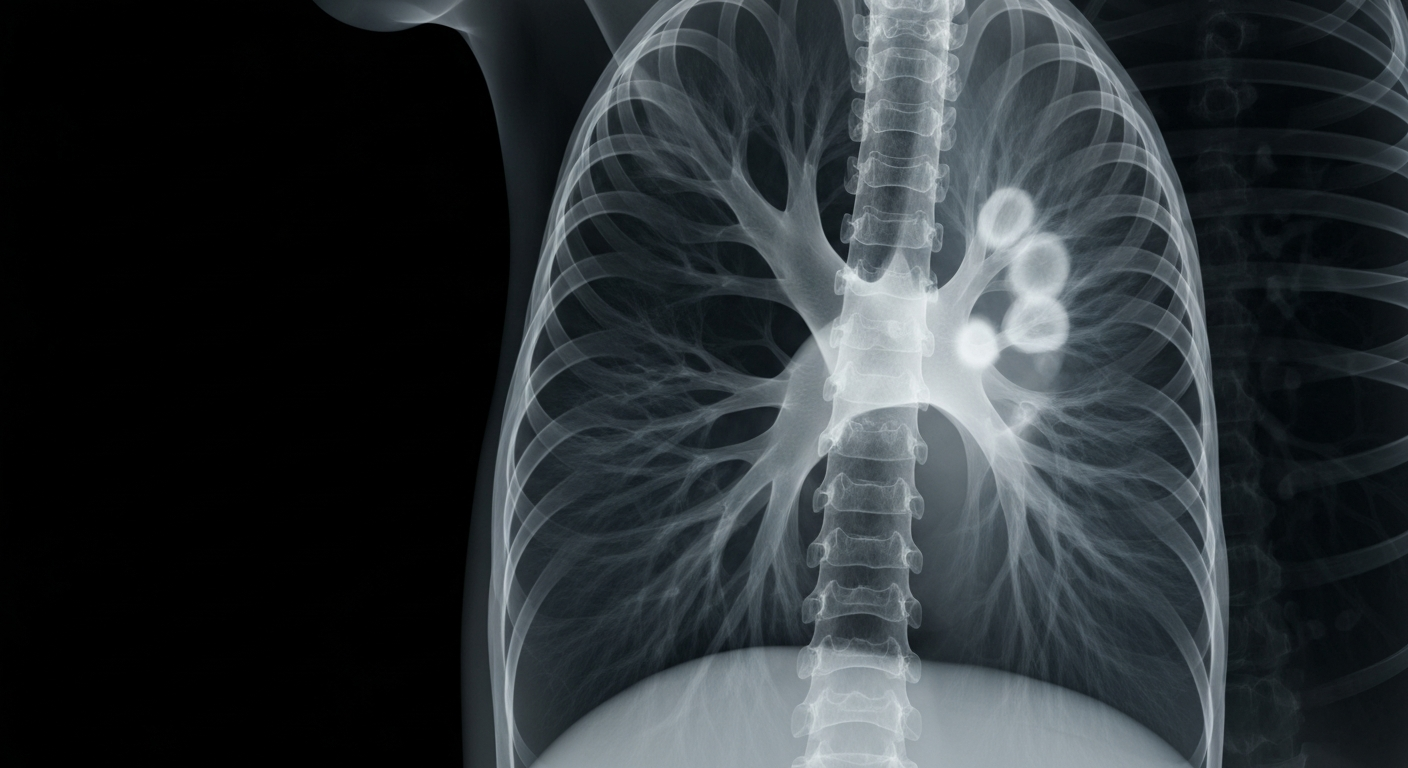

An X-ray view of the internal damage caused by COPD, highlighting the need for new treatment options to reduce exacerbations and improve lung health.Today in PittsburghAstraZeneca announced positive high-level results from the pivotal Phase III MIRANDA trial, which showed that tozorakimab, a potential first-in-class monoclonal antibody targeting interleukin-33 (IL-33), demonstrated a statistically significant and clinically meaningful reduction in the annualized rate of moderate-to-severe COPD exacerbations in the primary population of former smokers and in the overall population, including former and current smokers across all blood eosinophil counts and lung function severity levels.

COPD is the third leading cause of death globally, and up to half of patients still experience exacerbations even when taking standard-of-care inhaled therapies, putting them at risk of serious health consequences. These results add to the growing body of evidence that tozorakimab, with its unique mechanism of action, could provide a much-needed new treatment option for COPD patients.

A progressive respiratory condition characterized by persistent airflow limitation and chronic inflammation of the airways, which can lead to exacerbations that have a profound impact on patients' lives.